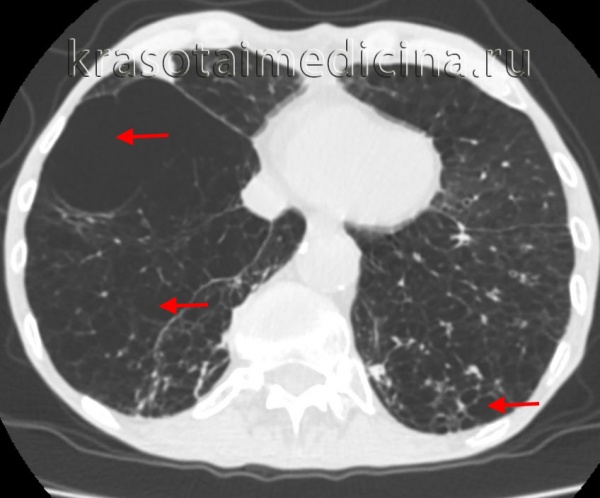

Буллезная эмфизема легкого – это локальные изменения легочной ткани, характеризующиеся деструкцией альвеолярных перегородок и формированием воздушных кист диаметром более 1 см (булл). При неосложненном течении буллезной эмфиземы легких симптомы могут отсутствовать вплоть до возникновения спонтанного пневмоторакса. Диагностическое подтверждение буллезной эмфиземы легких достигается с помощью рентгенографии, КТ высокого разрешения, сцинтиграфии, торакоскопии. При бессимптомной форме возможно динамическое наблюдение; в случае прогрессирующего или осложненного течения буллезной болезни легких проводится хирургическое лечение (буллэктомия, сегментэктомия, лобэктомия).

Диагностика буллезной эмфиземы легких основывается на клинических, функциональных и рентгенологических данных. Курация больного осуществляется пульмонологом, а при развитии осложнений – торакальным хирургом. Рентгенография легких не всегда эффективна в выявлении буллезной эмфиземы легких. В то же время, возможности лучевой диагностики существенно расширяет внедрение в практику КТ высокого разрешения. На томограммах буллы определяются как тонкостенные полости с четкими и ровными контурами. При сомнительном диагнозе удостовериться в наличии булл позволяет диагностическая торакоскопия.